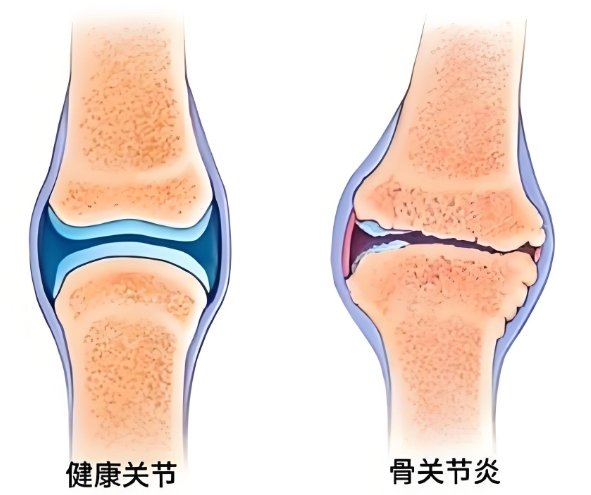

很多年轻人觉得,骨关节炎离自己很遥远,但实际上,骨关节炎从不是老年人的“专属”,年轻人也可能被它盯上。体重超标让关节长期承受超负荷压力,剧烈运动后的关节损伤、创伤后缺乏及时科学治疗,或是长期不良姿势、关节过度使用,都可能加速关节软骨的磨损与退化,进而引发骨关节炎。那么,罹患骨关节炎该如何治疗呢?氨糖就是常见的核心临床治疗药物。不过,它还分OTC硫酸氨糖和氨糖软骨素钙片,这二者又有什么区别,骨关节炎患者该选谁呢?